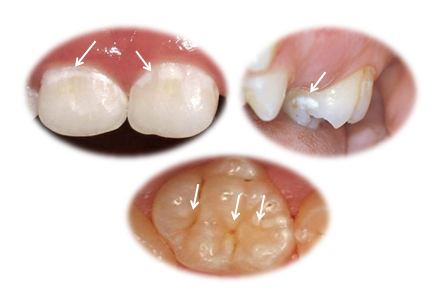

Prvi znaci topljenja gleđi su bele mrlje.(Slika 1.) One se lako uočavaju na vidljivim i griznim površnama zuba, i to su mesta gde se najpre i najbrže razvija rani karijes, naziva se još i „cirkularni karijes“, i od njega već do druge godine oboljeva 15%, a u periodu 3 – 5 godina čak 50% naše dece. Ovakva lokalizacija se lako uočava na običnom pregledu i pravovremenom intervencijom je moguće lako da se spreči pucanje.

Slika 1. Početni znak karijesa(topljenja zubne gleđi) su bele mrlje na tipičnim mestima: vrat zuba, grizne površine i bočne površine koje se uglavnom ne vide.